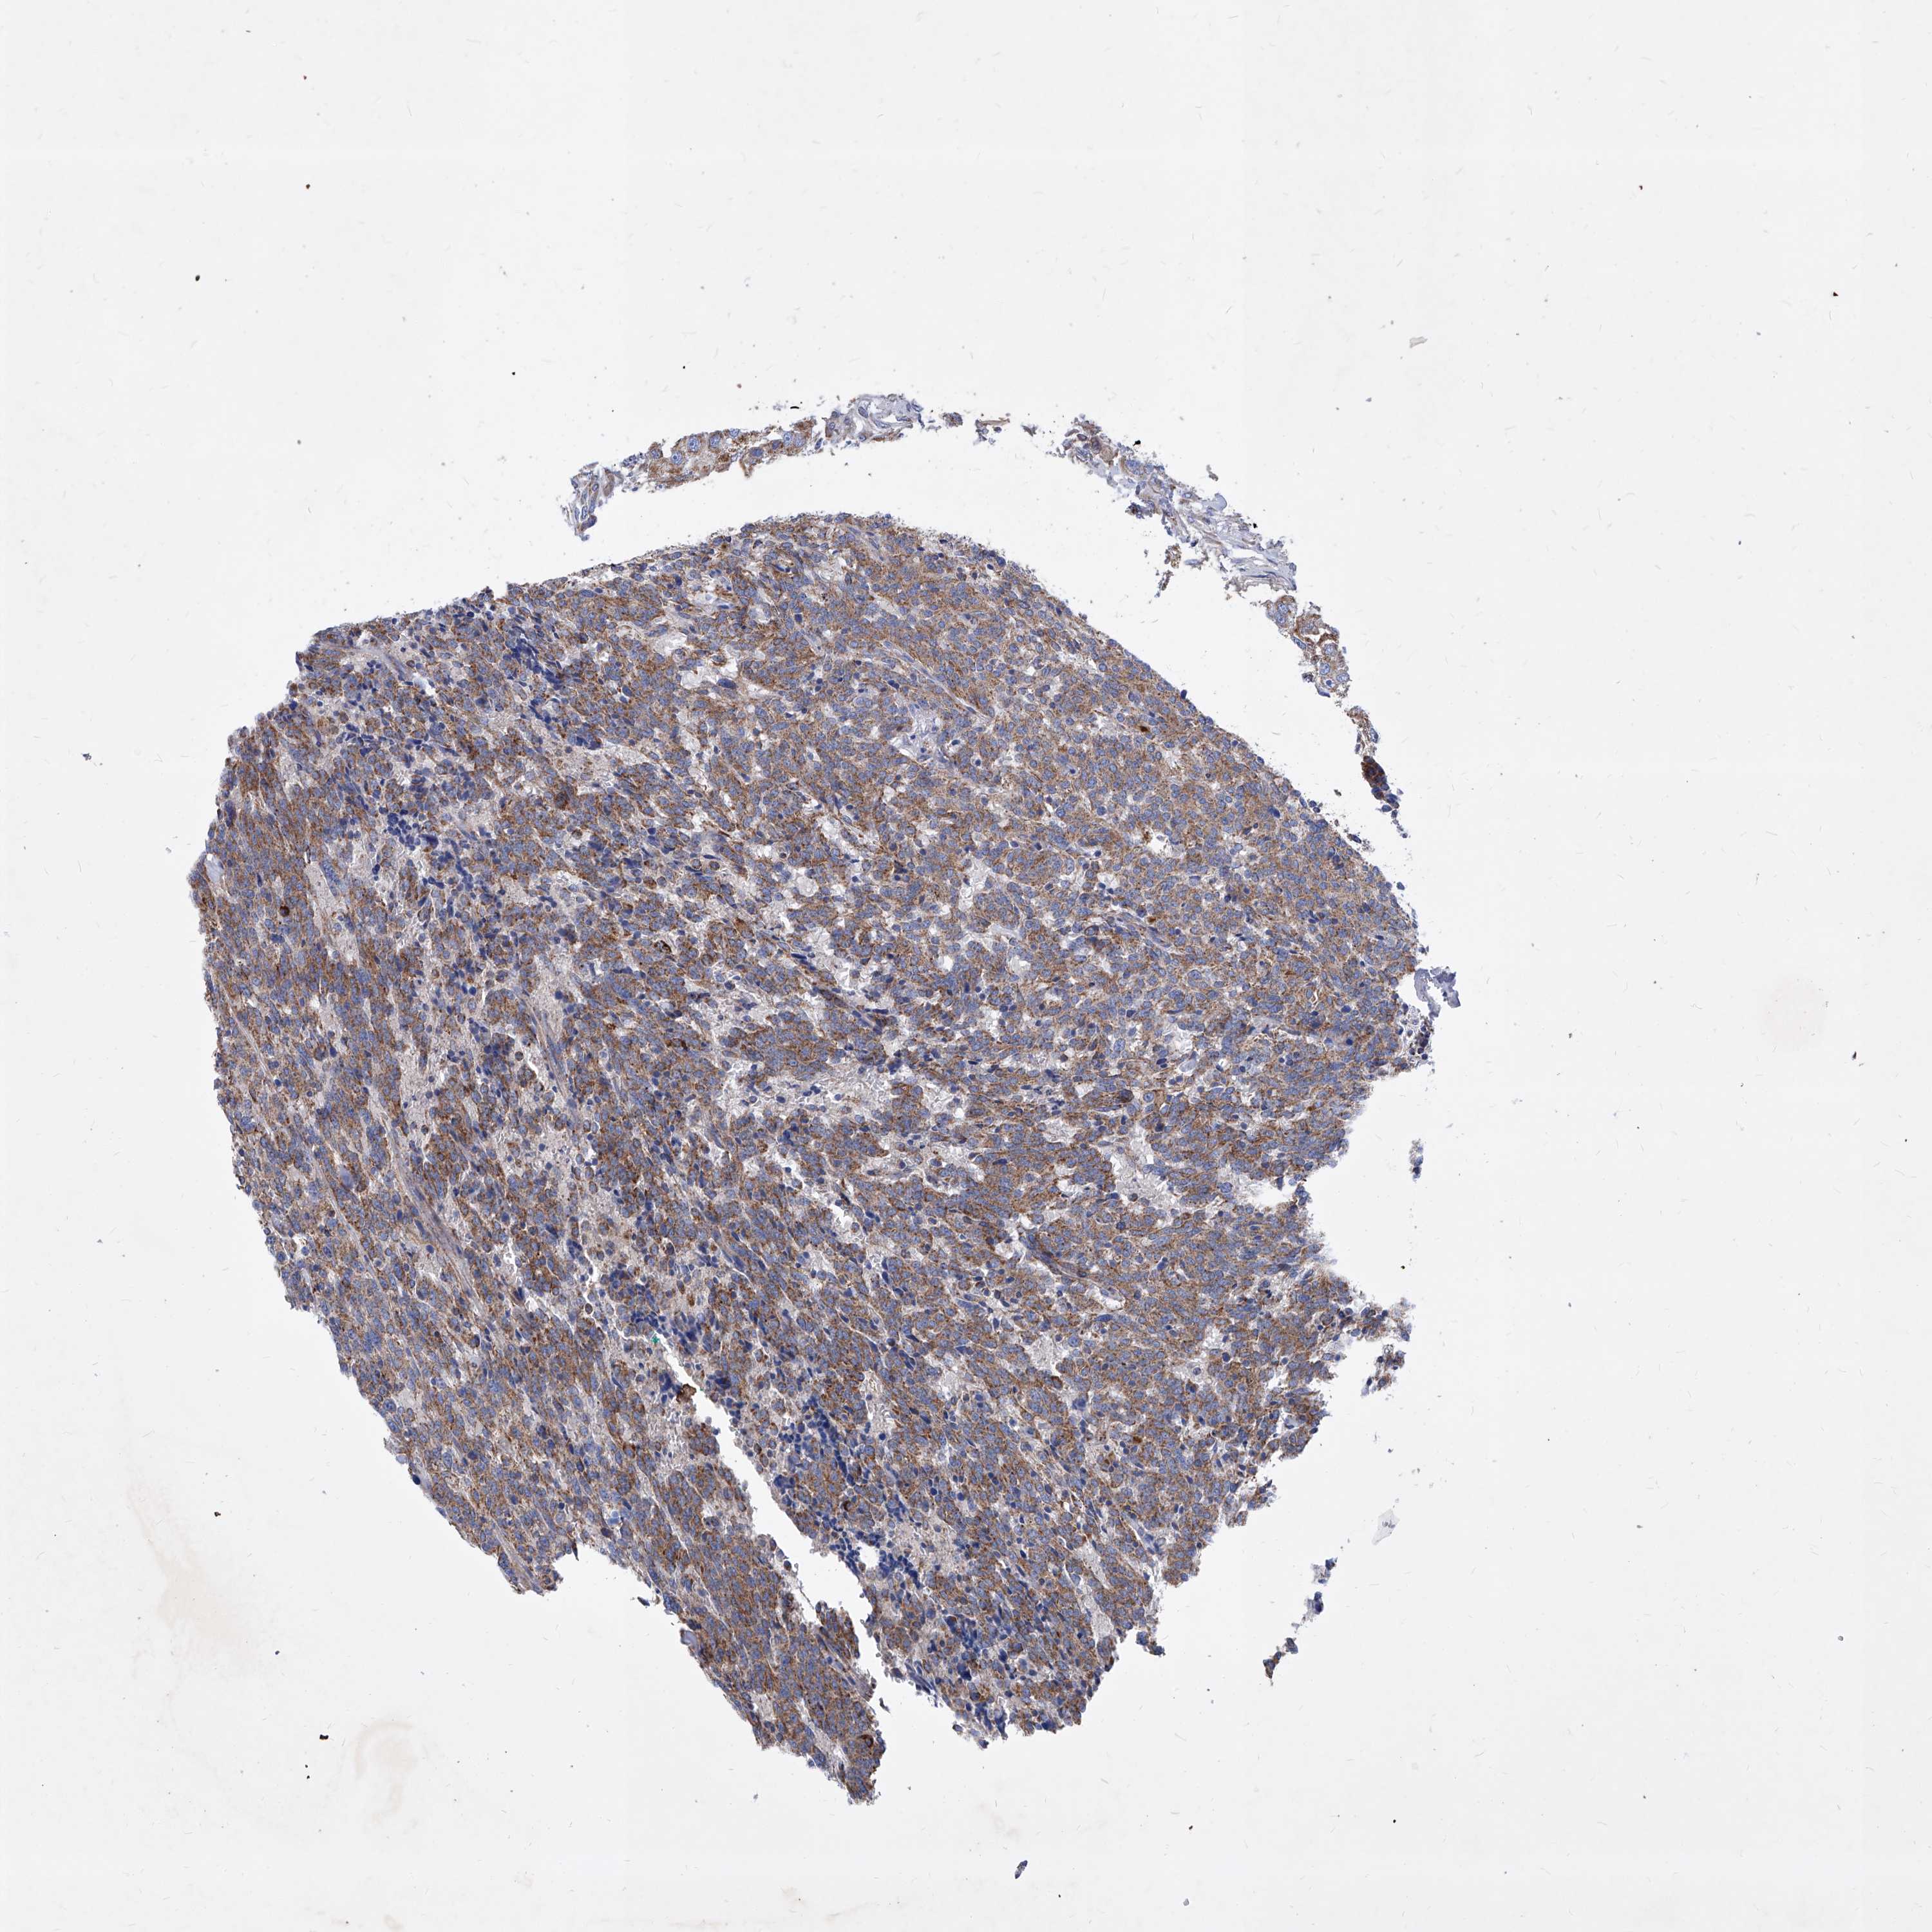

CARCINOID - Protein expressioni

A mouse-over function shows sample information and annotation data. Click on an image to view it in a full screen mode. Samples can be filtered based on level of antibody staining by selecting one or several of the following categories: high, medium, low and not detected. The assay and annotation is described here.

Antibody stainingi

Antibody staining in the annotated cell types in the current human tissue is reported as not detected, low, medium, or high, based on conventional immunohistochemistry profiling in selected tissues. This score is based on the combination of the staining intensity and fraction of stained cells.

Each image is clickable and will lead to virtual microscopy that enables deeper exploration of all samples and also displays staining intensity scores, fraction scores and subcellular localization as well as patient and tissue information for each sample.

Antibody HPA031469

Staining

High

Medium

Low

Not detected

Intensity

Strong

Moderate

Weak

Negative

Quantity

>75%

75%-25%

<25%

None

Location

Nuclear

Cytoplasmic/membranous

Cytoplasmic/membranous,nuclear

Carcinoid, malignant, NOS

Carcinoma, NOS